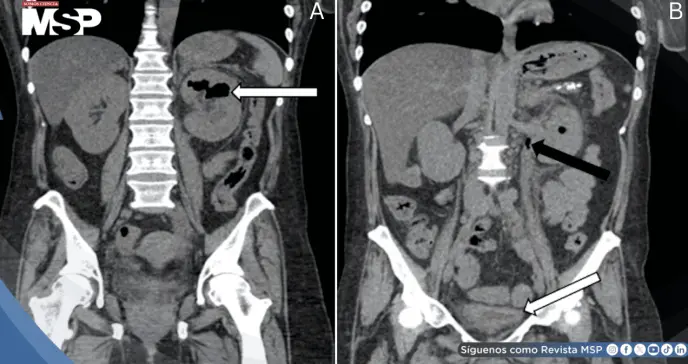

Durante la reevaluación, ante el deterioro clínico con taquicardia y dolor progresivo, se realizó tomografía computarizada de abdomen y pelvis sin contraste. Las imágenes demostraron hidronefrosis izquierda con presencia de gas en el sistema colector renal, hallazgo patognomónico de pielitis enfisematosa.

También se identificó hidrouréter, engrosamiento de la pared vesical y edema perivesical, sugiriendo propagación ascendente de la infección.

Tras un curso hospitalario complejo pero favorable, la paciente fue dada de alta. El seguimiento a 36 días con nueva tomografía computarizada documentó resolución completa de los hallazgos radiológicos. El tubo de nefrostomía se retiró al día 37 sin complicaciones posteriores.